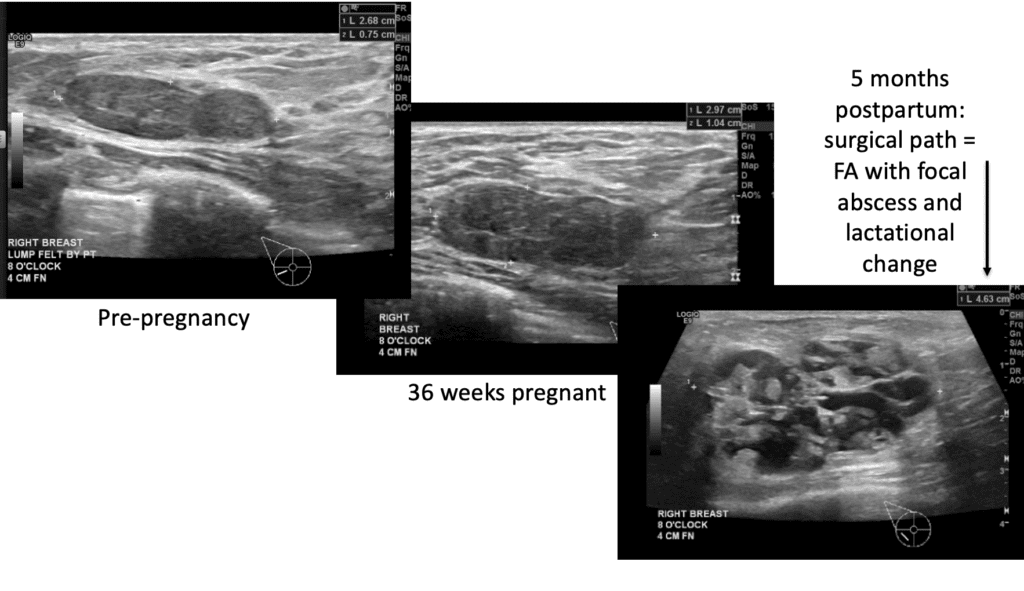

Fibroadenoma

Fibroadenomas are the most common benign (non-cancerous) growth of the breast. Fibroadenomas grow during pregnancy and lactation, and can significantly change appearance on ultrasound. Therefore, biopsy to confirm diagnosis prior to pregnancy is very important. If the lesion is not able to be confirmed fibroadenoma and is designated a non-specific fibroepithelial lesion, the patient should undergo excision to determine whether the lesion is a fibroadenoma or a phyllodes tumor (which can grow more rapidly and may not always be benign).

The video below demonstrates removal of a phyllodes lesion during lactation. There are several things to learn from this video:

- Breast imaging, breast biopsy, and breast surgery are safe during pregnancy and lactation. In fact, it would have been more ideal to remove this mass during pregnancy (before it grew and to rule out anything worrisome like a malignant phyllodes tumor). It also is far easier to operate without complication on a pregnant, rather than lactating, breast.

- In retrospect, this patient would have benefitted from a drain post-operatively rather than repeated aspirations.

- Breastmilk is under autocrine (local – i.e. the breasts function independently) control after two weeks postpartum (the first two weeks are endocrine, or central control). This means you can upregulate and downregulate the breasts independently.

- It is very important to treat hyperlactation (overproduction of breastmilk) in general, as well is when it is present when a patient requires surgery.